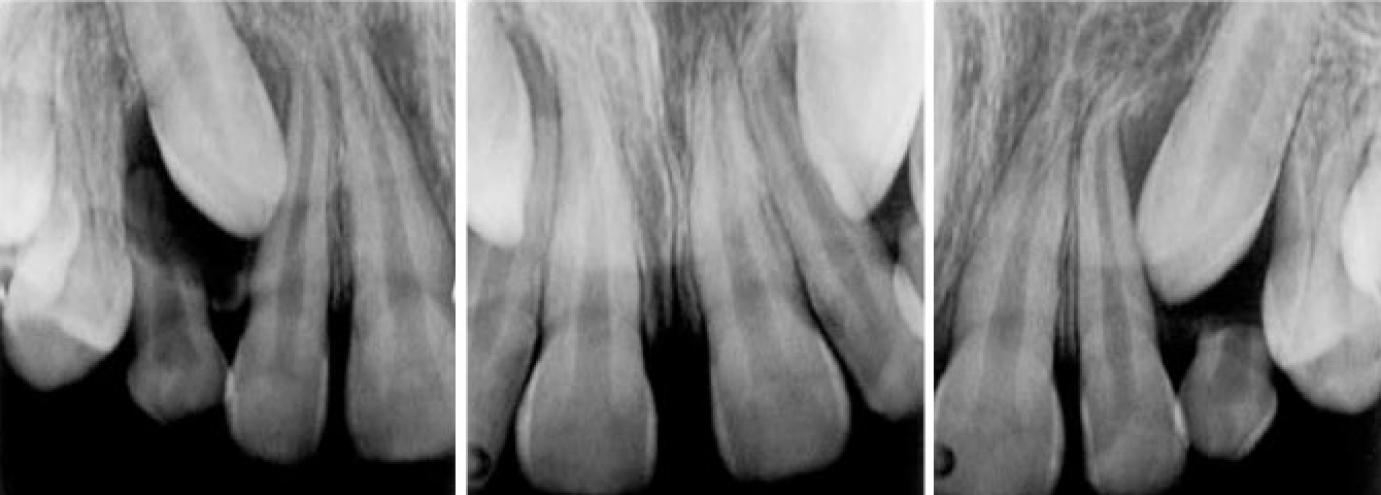

Az első fogszabályozási konzultáció alkalmával gyakran jelentkező probléma bizonyos fogak előtörés előtti hibás tengelyállása. Legtöbbször a szemfogak pozícióhibájáról beszélhetünk, mely a súlyos, előtöréssel összeegyeztethetetlen állapottól, egészen a pár fokos eltérésekig terjedhet. Előfordul, hogy ez az eltérés pont olyan mértékű, hogy a maradó szemfog nem a tejszemfogat maga előtt kilökve, hanem beékelődve a maradó metsző és tejszemfog közé, közöttük próbál utat találni magának. Ezekben az esetekben a tej szemfog, illetve az első tejőrlő megfelelően időzített, azaz irányított eltávolításával van reményünk a maradó szemfogat a megfelelő útra terelni, ezzel elkerülve egy esetleges fogszabályozó kezelést.